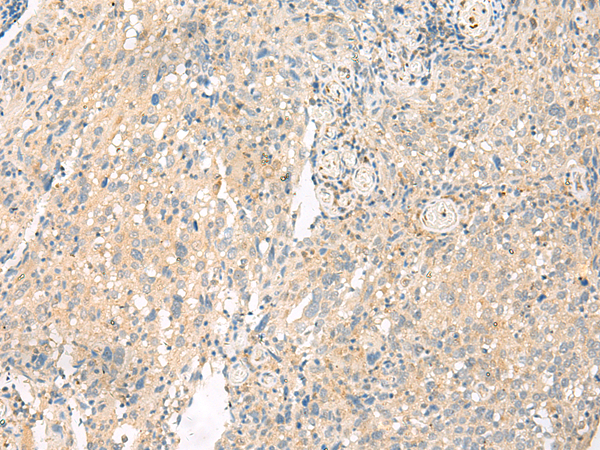

分类: 科研抗体货号: P04169别名: STHAG3应用: IHC反应种属: Human, Mouse, Rat